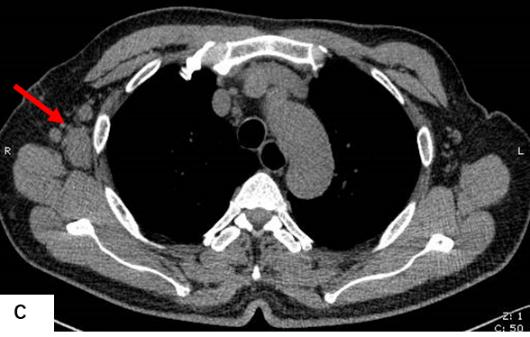

前列腺M(fèi)RI示:前列腺移行帶結(jié)節(jié)狀異常信號(hào),建議穿刺活檢;前列腺增生,PI-RADS2;雙側(cè)股骨頭信號(hào)異常,不排除轉(zhuǎn)移瘤(圖A)。為評(píng)估骨轉(zhuǎn)移情況遂行ECT全身骨顯像檢查,示:雙側(cè)肱骨頭、雙側(cè)股骨頭、右側(cè)前臂上段、右側(cè)股骨中下段代謝異常增強(qiáng)(圖B)。骨顯像不符合前列腺癌骨轉(zhuǎn)移典型表現(xiàn),同時(shí)結(jié)合患者胸部CT(圖C)平掃示右側(cè)腋窩多發(fā)淋巴結(jié)腫大,生化檢查示乳酸脫氫酶620U/L(97-270),懷疑系血液系統(tǒng)腫瘤,建議患者行PET/CT檢查。PET/CT示:右側(cè)腦室內(nèi)高密度灶,多發(fā)FDG代謝增高淋巴結(jié)及多發(fā)骨骼/骨髓FDG代謝增高灶,考慮淋巴瘤(圖D)。

胸部CT平掃示右側(cè)腋窩多發(fā)腫大淋巴結(jié)(紅箭)。